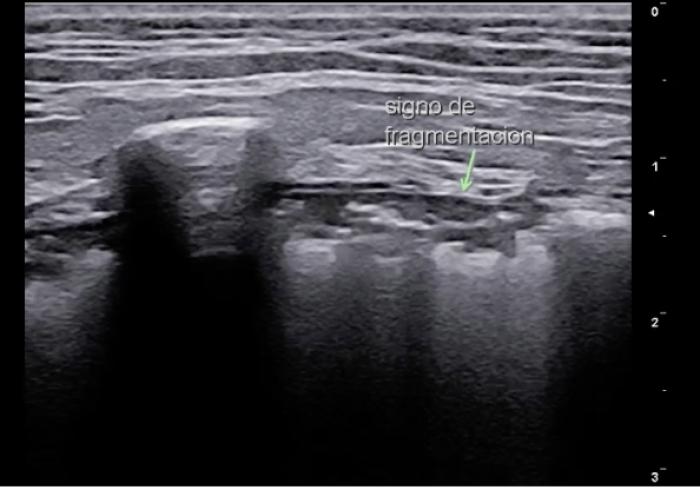

Signo de fragmentación

En inicio la consolidación pulmonar a nivel subpleural se produce cuando la aireación se encuentra por debajo del 10%. La comenzaremos viendo como focos irregulares bajo la LP que nos darán un aspecto irregular de la misma (Vídeo 8).

Paulatinamente estos focos aumentaran su extensión (pero restringiendo a parte de un lóbulo y no a su totalidad), generando unos bordes dentados en su transición con el pulmón aireado y con presencia de broncogramas en su interior, que definiremos como signo de fragmentación, desgarro o en “dientes de sierra”. Su presencia está ligada principalmente a la existencia de procesos bronco neumónicos o evolución de áreas de edema o contusión. Ocasionalmente pueden ser la imagen de una neoplasia cuando esta comienza a gestarse, de ahí la importancia de la anamnesis del paciente. Las líneas b suelen estar presentes en todas estas situaciones ya que suponen el inicio de nuevos puntos con falta de aireación (Figura 12A-D).